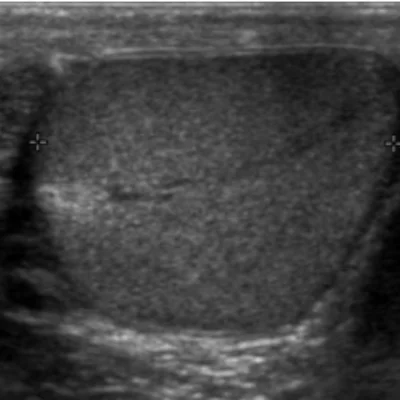

Small Parts Ultrasound

We provide targeted imaging for smaller anatomical regions

Thyroid

Detect nodules, goiters, or inflammation

Breast

Evaluate lumps, cysts, or post-mammography findings

Scrotum

Assess pain, swelling, or infertility-related issues

These scans are performed with precision and privacy, ensuring patient comfort and diagnostic accuracy.